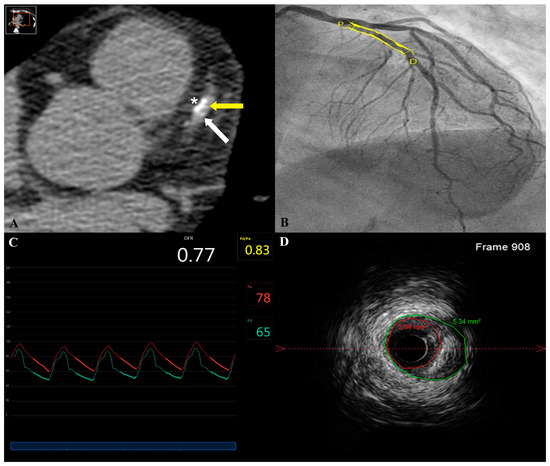

| n | 15 | 17 | 32 | |

| Date difference (months) | 7.1 ± 4.5 | 5.6 ± 2.5 | 6.4 ± 3.7 | NS |

| Proximal vessel diameter (mm) | 4.0 ± 0.3 | 3.8 ± 0.7 | 3.9 ± 0.5 | NS |

| Distal vessel diameter (mm) | 3.3 ± 0.6 | 3.1 ± 0.6 | 3.2 ± 0.6 | NS |

| Proximal surface area (mm2) | 9.4 ± 1.9 | 10.0 ± 3.7 | 9.7 ± 2.9 | NS |

| Distal surface area (mm2) | 7.4 ± 2.1 | 7.1 ± 2.9 | 7.2 ± 2.5 | NS |

| In-stent minimal diameter (mm) | 2.4 ± 0.4 | 2.4 ± 0.7 | 2.4 ± 0.6 | NS |

| In-stent maximal diameter (mm) | 4.1 ± 0.5 | 3.9 ± 0.9 | 4.0 ± 0.8 | NS |

| Minimal in-stent surface area (MSA) (mm2) | 6.1 ± 1.2 | 6.8 ± 2.6 | 6.5 ± 2.0 | NS |

| Maximal in-stent surface area (mm2) | 11.3 ± 2.5 | 10.9 ± 3.4 | 11.1 ± 3.0 | NS |

| Mean proximal to distal surface area (mm2) | 8.4 ± 1.6 | 8.5 ± 2.9 | 8.4 ± 2.3 | NS |